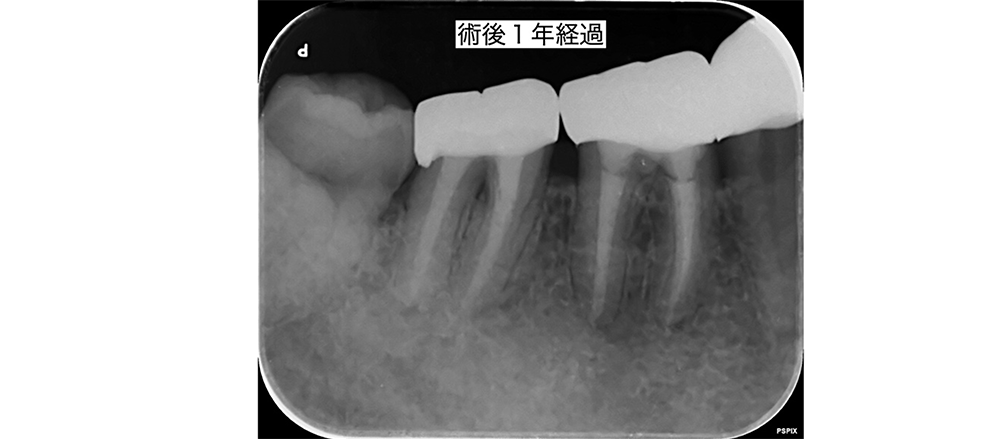

金山デンタルクリニックでは、治療の前に必ずCT撮影を行い、神経の本数や根の形、病変の大きさを正確に診査。治療の可能性や成功率まで含め、CTの画像を見せながら丁寧にご説明しています。治療後の経過もマイクロスコープやCT画像をお見せしながら、ご説明させていただきます。

金山デンタルクリニックでは、再治療が難しい症例や、根の先に大きな病変がある症例に対し、歯根端切除術などの外科的処置も行っています。

学会ガイドラインに基づく外科的歯内療法では、80〜90%の成功率が報告されており(※AAEガイドライン等)、正しい手順を踏めば、まだ歯を残せる可能性は十分にあります。